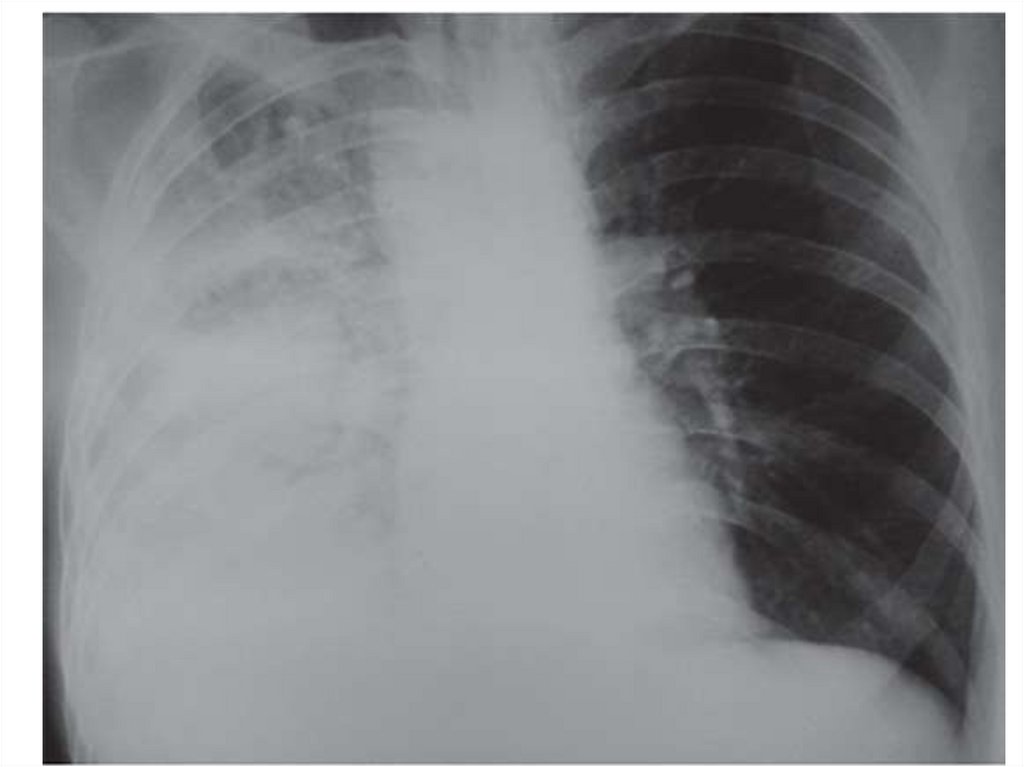

Пневмоторакс